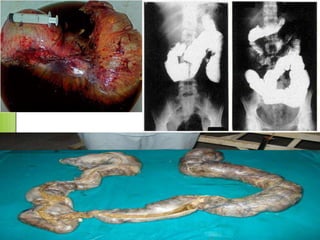

Hepatoesplenomegalia, miocarditis e

hipertrofia del esófago y el colon, como          La cardiomegalia y las

consecuencia de la destrucción de las                 alteraciones

Fase crónica

células nerviosas (plexo de Auerbach) y            electrocardiográficas

otros tejidos encargados de controlar el              son comunes.

tamaño de estos órganos.

En la esofagopatía hay

Insuficiencia

trastornos de la                   Un número no

cardíaca y

motilidad que provocan                determinado de

Formas crónicas                 tromboembolias.

disfagia, dolor                pacientes desarrolla

digestivas                 Puede ocurrir muerte

epigástrico o                   megaesófago y

súbita por fibrilación

retroesternal y                    megacolon.

ventricular.

regurgitaciones.

El megacolon se manifiesta

En las etapas avanzadas el                     clínicamente por                     Un cuadro de dolor

esófago prácticamente no              constipación, que en un principio            abdominal agudo

transporta su contenido,                 responde a la acción de                  debe hacer pensar

con la consecuente                laxantes, pero luego se produce              en un vólvulo

desnutrición, y retraso de            retención de la materia fecal por            sigmoideo por

crecimiento en niños.                10 días o más, produciendo                 torsión colónica.

fecaloma.